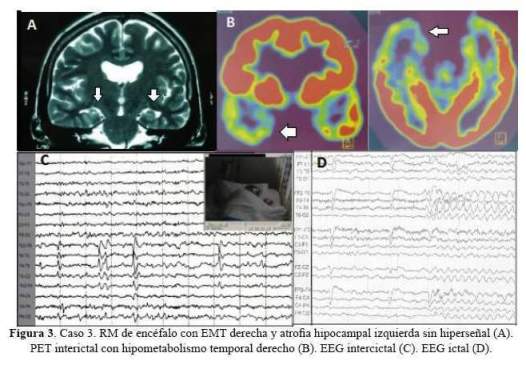

De los 5 casos, 3 cirugías correspondieron a pacientes con epilepsia temporal mesial derecha (2 por esclerosis mesial temporal y 1 por ganglioglioma mediobasal temporal anterior) y 2 correspondieron a patología dual (1 con EMT derecha más lesión gliótica cicatrizal de un angioma cavernoso temporal neocorical ipsilateral operado previamente y 1 con EMT izquierda más gliosis frontal ipsilateral). De los 3 pacientes con epilepsia temporal mesial derecha, 2 sólo requirieron de estudios paraclínicos en fase 1: EEG/VideoEEG y RM encéfalo estructural y 1 requirió además de PET interictal (fase 2), pues a pesar de que la semiología y actividad electrográfica ictal correspondían a una epilepsia del lóbulo temporal mesial derecho, la RM de encéfalo dejaba duda respecto a si además de tener EMT derecha,tenía también EMT izquierda. A estos tres pacientes se les realizó lobectomía temporal anteromesial (LTA) que incluyó amigdalohipocampectomía, siguiendo las técnicas quirúrgicas del Programa de Epilepsia del London Health Sciences Centre, University of Western Ontario, Canadá (20). Las 2 pacientes con patología dual fueron intervenidas con el apoyo de electrocorticografía (ECoG) aguda o intraoperatoria. En una de ellas se demostró que la lesión frontal izquierda ipsilateral era silente, no se resecó y se realizó solo LTA izquierda. En la otra paciente, la ECoG orientó a realizar una lesionectomía ampliada de la lesión neocortical temporal anterior; pero tuvimos que abstenernos de realizar una amgdalohipocampectomía a pesar de tratarse de una patología dual, pues su reserva cognitiva y la memoria, tanto verbal como visual estaban indemnes. Es importante señalar que en ésta paciente la semiología ictal inicial era neocortical (auras auditivas, seguidas solo después de segundos de miedo). En la primera paciente con patología dual además se realizó estimulación cortical directa para la evaluación intraoperatoria del lenguaje con la paciente despierta; se puede revisar en detalle el procedimiento en un reporte del caso publicado previamente (21). No se realizaron en esta serie resecciones extratemporales. Los resultados de anatomopatología evidenciaron como etiología definitiva: 3 EMT, 1 ganglioglioma y 1 gliosis reactiva; esta última corresponde a la paciente con patología dual con lesión gliótica cicatrizal neocortical temporal derecha, operada en años previos de angioma cavernoso en dicha zona. Las imágenes de RM de encéfalo y EEG de los casos 1, 2, 3 y 5 pueden ser revisadas en la figura 1,figura 2,figura 3 y figura 4 Las imágenes del caso 4 pueden ser revisadas en un reporte de caso publicado previamente (21).